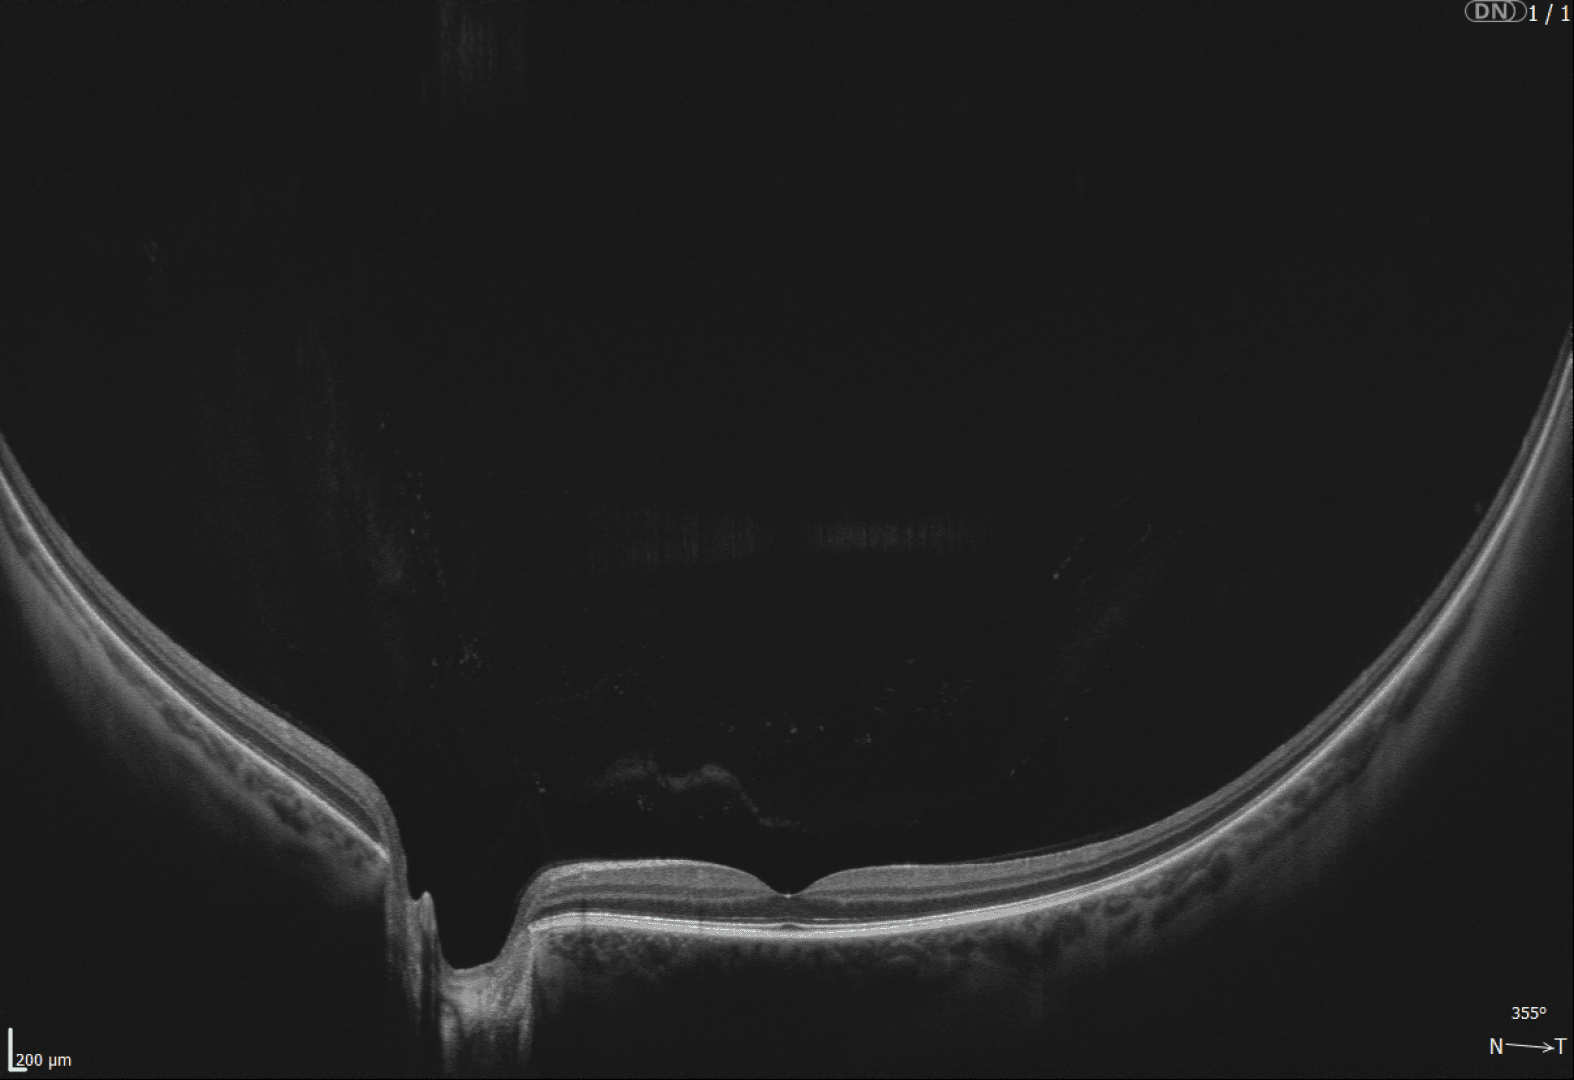

Alle Modelle überzeugen durch ihre Vollausstattung: Netzhaut-Screening, Glaukom-Analyse, Vorderabschnitt-Scans, Gonioskopie und Pachymetrie - alles vollautomatisch und gestützt durch eine normative Datenbank zur unabhängigen Befundbewertung. Optional erweitern Funktionen wie Biometrie, Hornhauttopographie und OCT-Angiographie die Einsatzmöglichkeiten.